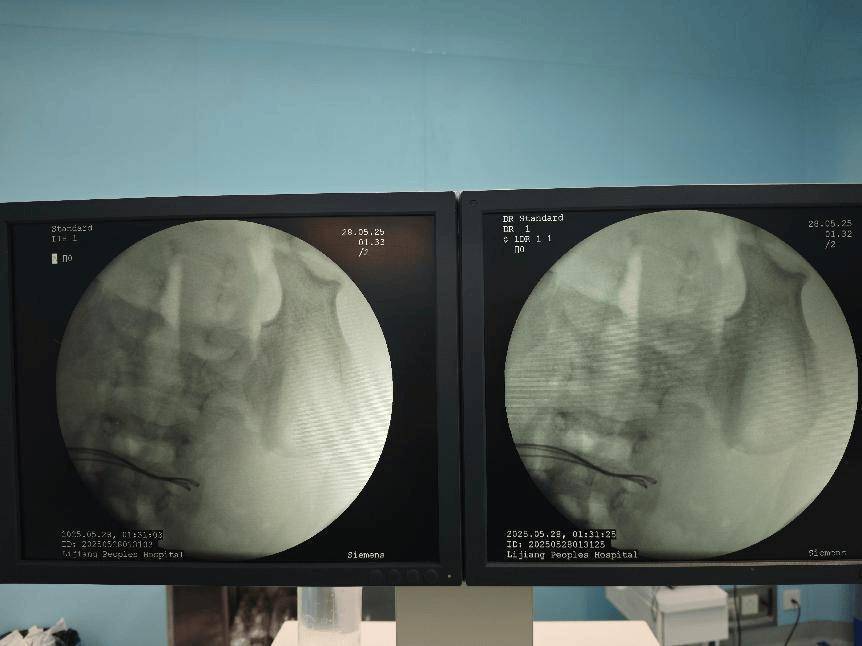

术前腹部DR片

经过初步的影像学检查,医疗团队发现:病人体内竟然有37颗异物,连在一起呈手串状,并伴有小肠穿孔。

面对如此严重的病情,丽江市人民医院普外一科立即启动了紧急救治程序,组织专家团队进行会诊,并制定出了周密的手术方案。但手术过程中,医疗团队发现了比预想中更为复杂的情况:病人小肠内的异物竟然是被称为无声“肠道杀手”的磁力珠。